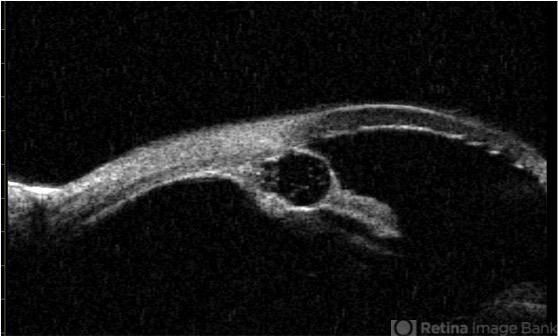

- Epithelial iris cyst

- UBM of the right eye showing a peripheral iris cyst with a smaller cyst inside of it.